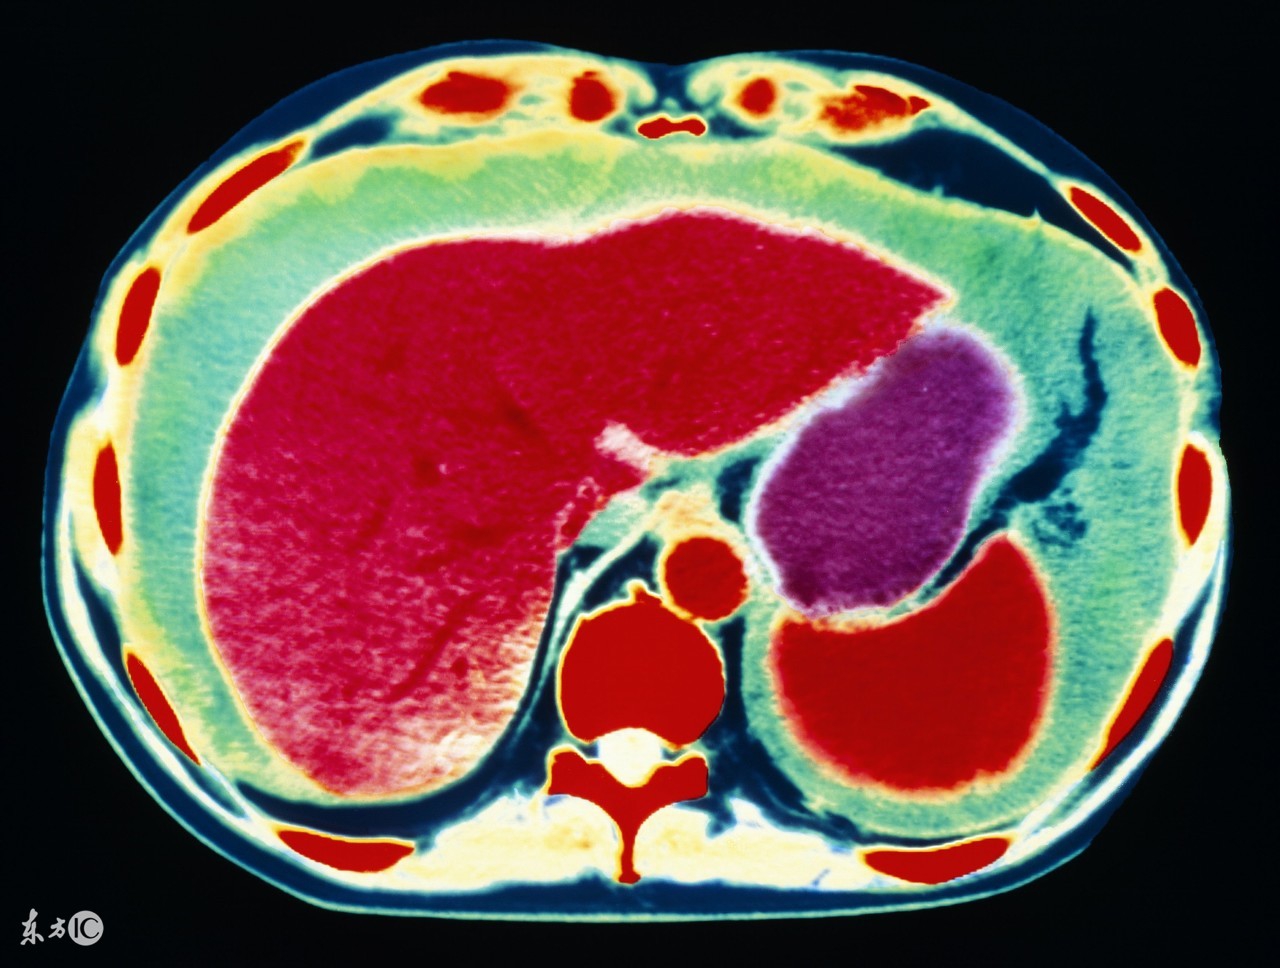

1、肝癌。前面说了,肝病是引起腹水最常见的原因,其中肝癌就是其一。原发性肝癌,发展到一定程度,合并腹水的可能性非常大,其实本质上仍是肝硬化所致,所以肝腹水就是肝硬化腹水。肝硬化时,肝细胞变性、坏死、纤维组织增生,肝内血管床受压、扭曲、变形、狭窄,阻塞了血管,使肝窦淤血,血流量大大降低,门静脉压力升高,同时,毛细血管静脉压力也升高,久而久之,胃肠道、肠系膜、腹膜等血液回流受阻,血管通透性升高,血液中的血浆成分外漏,形成了腹水。肝功能不合,肝脏不能合成白蛋白,低蛋白血症,由于血清白蛋白的降低,血管内胶体渗透压下降,血浆成分外渗而形成腹水。所以,不管什么肝病,到了肝硬化,肝功能不全的阶段,就可能形成腹水。